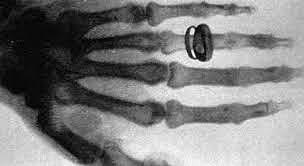

Descubrimiento de la Radiología

El físico alemán Roentgen descubrió los rayos x mientras realizaba un experimento con tubos de vació y un generador eléctrico.